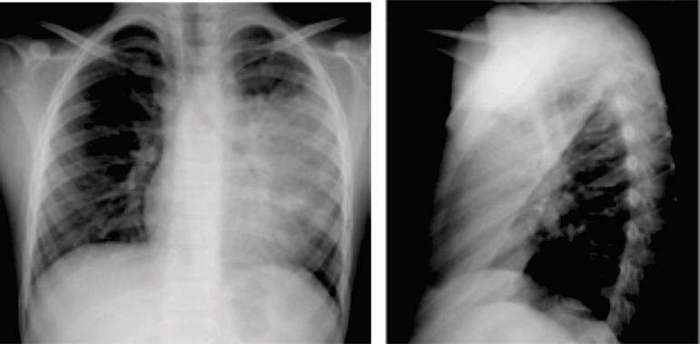

Um paciente de 36 anos de idade procurou atendimento médico queixando-se de tosse produtiva com escarro purulento, febre alta com calafrios e dor pleurítica à esquerda. Negou comorbidades e tabagismo. Ao exame físico, observava-se PA de 121 x 79 mmHg, FC de 106 bpm, FR de 23 irpm, Sat. de o2 de 94% em ar ambiente, com temperatura axilar de 38,8 ⁰C. O exame do tórax registrou a presença de murmúrio vesicular reduzido à esquerda. O hemograma mostrou leucocitose de 18.000 com 4% de bastões, sendo que eletrólitos e função renal e hepática estavam normais. A radiografia de tórax obtida na admissão é a seguinte: